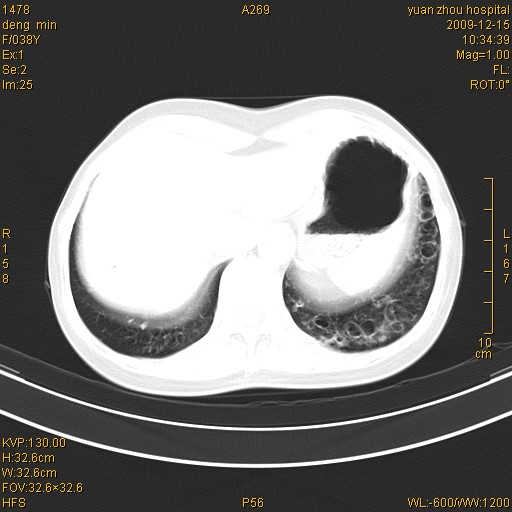

标题: CT23919:F38Y 咳嗽月余 [打印本页]

标题: CT23919:F38Y 咳嗽月余

右肺中下叶、左肺上叶舌段及左肺下叶支气管扩张合并感染。